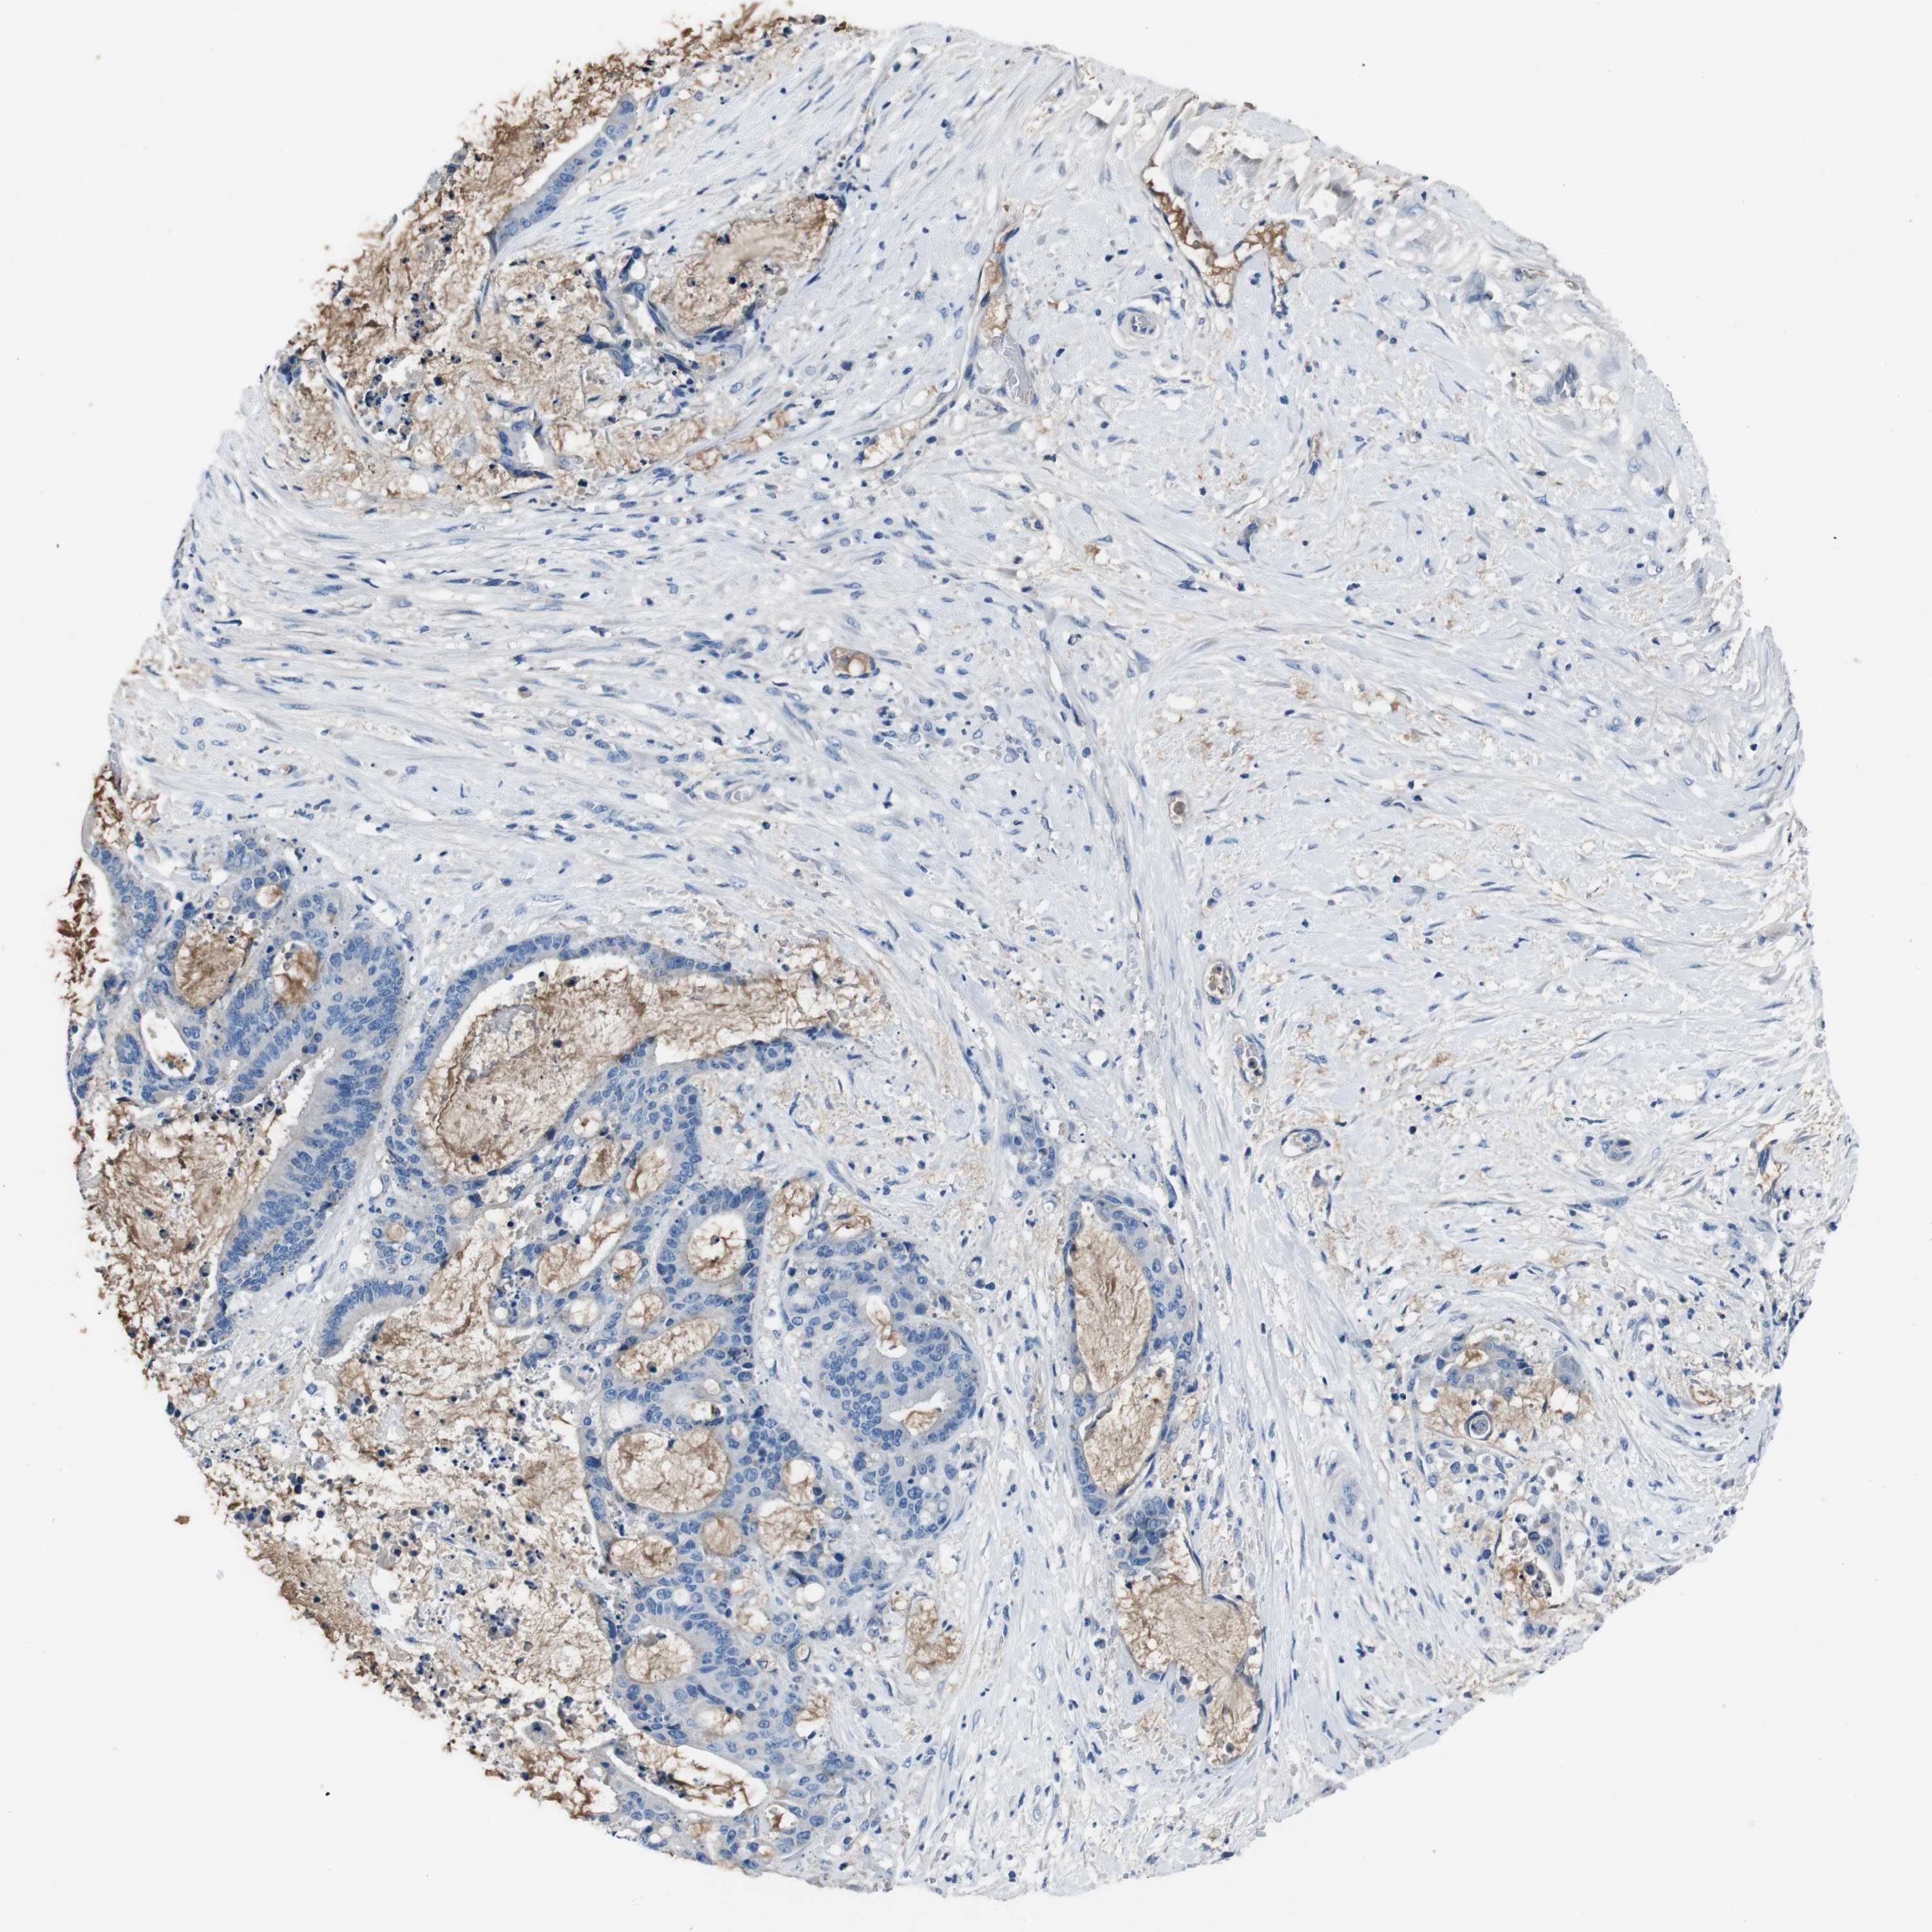

LIVER CANCER - Protein expressioni

A mouse-over function shows sample information and annotation data. Click on an image to view it in a full screen mode. Samples can be filtered based on level of antibody staining by selecting one or several of the following categories: high, medium, low and not detected. The assay and annotation is described here.

Note that samples used for immunohistochemistry by the Human Protein Atlas do not correspond to samples in the TCGA dataset.

Antibody stainingi

Antibody staining in the annotated cell types in the current human tissue is reported as not detected, low, medium, or high, based on conventional immunohistochemistry profiling in selected tissues. This score is based on the combination of the staining intensity and fraction of stained cells.

Each image is clickable and will lead to virtual microscopy that enables deeper exploration of all samples and also displays staining intensity scores, fraction scores and subcellular localization as well as patient and tissue information for each sample.

Antibody CAB010490

Staining

High

Medium

Low

Not detected

Intensity

Strong

Moderate

Weak

Negative

Quantity

>75%

75%-25%

<25%

None

Location

Nuclear

Cytoplasmic/membranous

Cytoplasmic/membranous,nuclear

Cholangiocarcinoma

Carcinoma, Hepatocellular, NOS